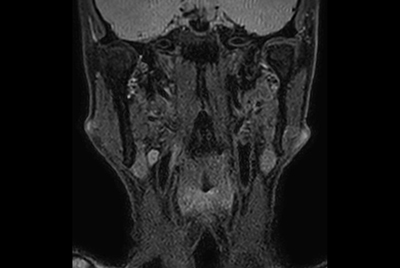

Soft Tissue of the neck